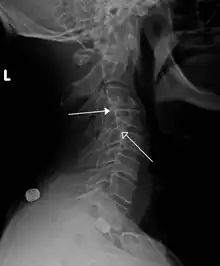

| X-ray of the lateral lumbar spine with a grade III anterolisthesis at the L5-S1 level | |

Classification by degree of the slippage, as measured as percentage of the width of the vertebral body:[14] Grade I spondylolisthesis accounts for approximately 75% of all cases.[6]

- Grade I: 0–25%

- Grade II: 25–50%

- Grade III: 50–75%

- Grade IV: 75–100%

- Grade V: greater than 100%

X-ray of measurement of spondylolisthesis at the lumbosacral joint, being 25% in this example

X-ray of measurement of spondylolisthesis at the lumbosacral joint, being 25% in this example X-ray picture of a grade 1 isthmic anterolisthesis at L4-5

X-ray picture of a grade 1 isthmic anterolisthesis at L4-5 MRI of L5-S1 anterolisthesis

MRI of L5-S1 anterolisthesis X-ray of a grade 4 anterolisthesis at L5-S1 with spinal misalignment indicated

X-ray of a grade 4 anterolisthesis at L5-S1 with spinal misalignment indicated Anterolisthesis L5/S1

Anterolisthesis L5/S1 Anterolisthesis L5/S1

Anterolisthesis L5/S1 Anterolisthesis L5/S1. Blue arrow normal pars interarticularis. Red arrow is a break in pars interarticularis.

Anterolisthesis L5/S1. Blue arrow normal pars interarticularis. Red arrow is a break in pars interarticularis. Anterolisthesis L5/S1

Anterolisthesis L5/S1

Plain Radiography (X-Ray)

Plain radiography is often the first step in medical imaging.[17] Anteroposterior (front-back) and lateral (side) images are used to allow the physician to view the spine at multiple angles.[17] Oblique view are no longer recommended.[28][29] In evaluating for spondylolithesis, plain radiographs provide information on the positioning and structural integrity of the spine. Therefore, if further detail is needed, a physician may request advanced imaging.